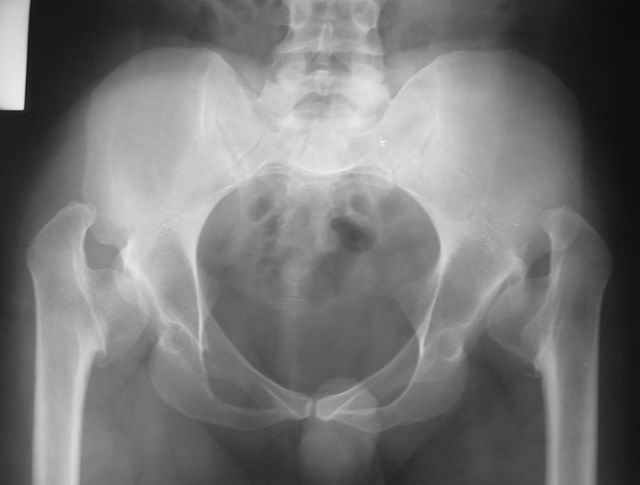

Congenital coxa vara

Dear All, This 27 year old presented to a colleague, about 2 years back, with complaints of bilateral hip pain. He was treated symptomatically, but now has increasing pain, and walking distance is being limited.

On examination, he has got a lordotic gait, Trendelenberg negative, bilaterally, hip movements fairly good, with no FFD. X-rays are attached. Kindly give your opinions regarding management and future prognosis. Thanks and regards Muhammad Amin Chinoy FRCS